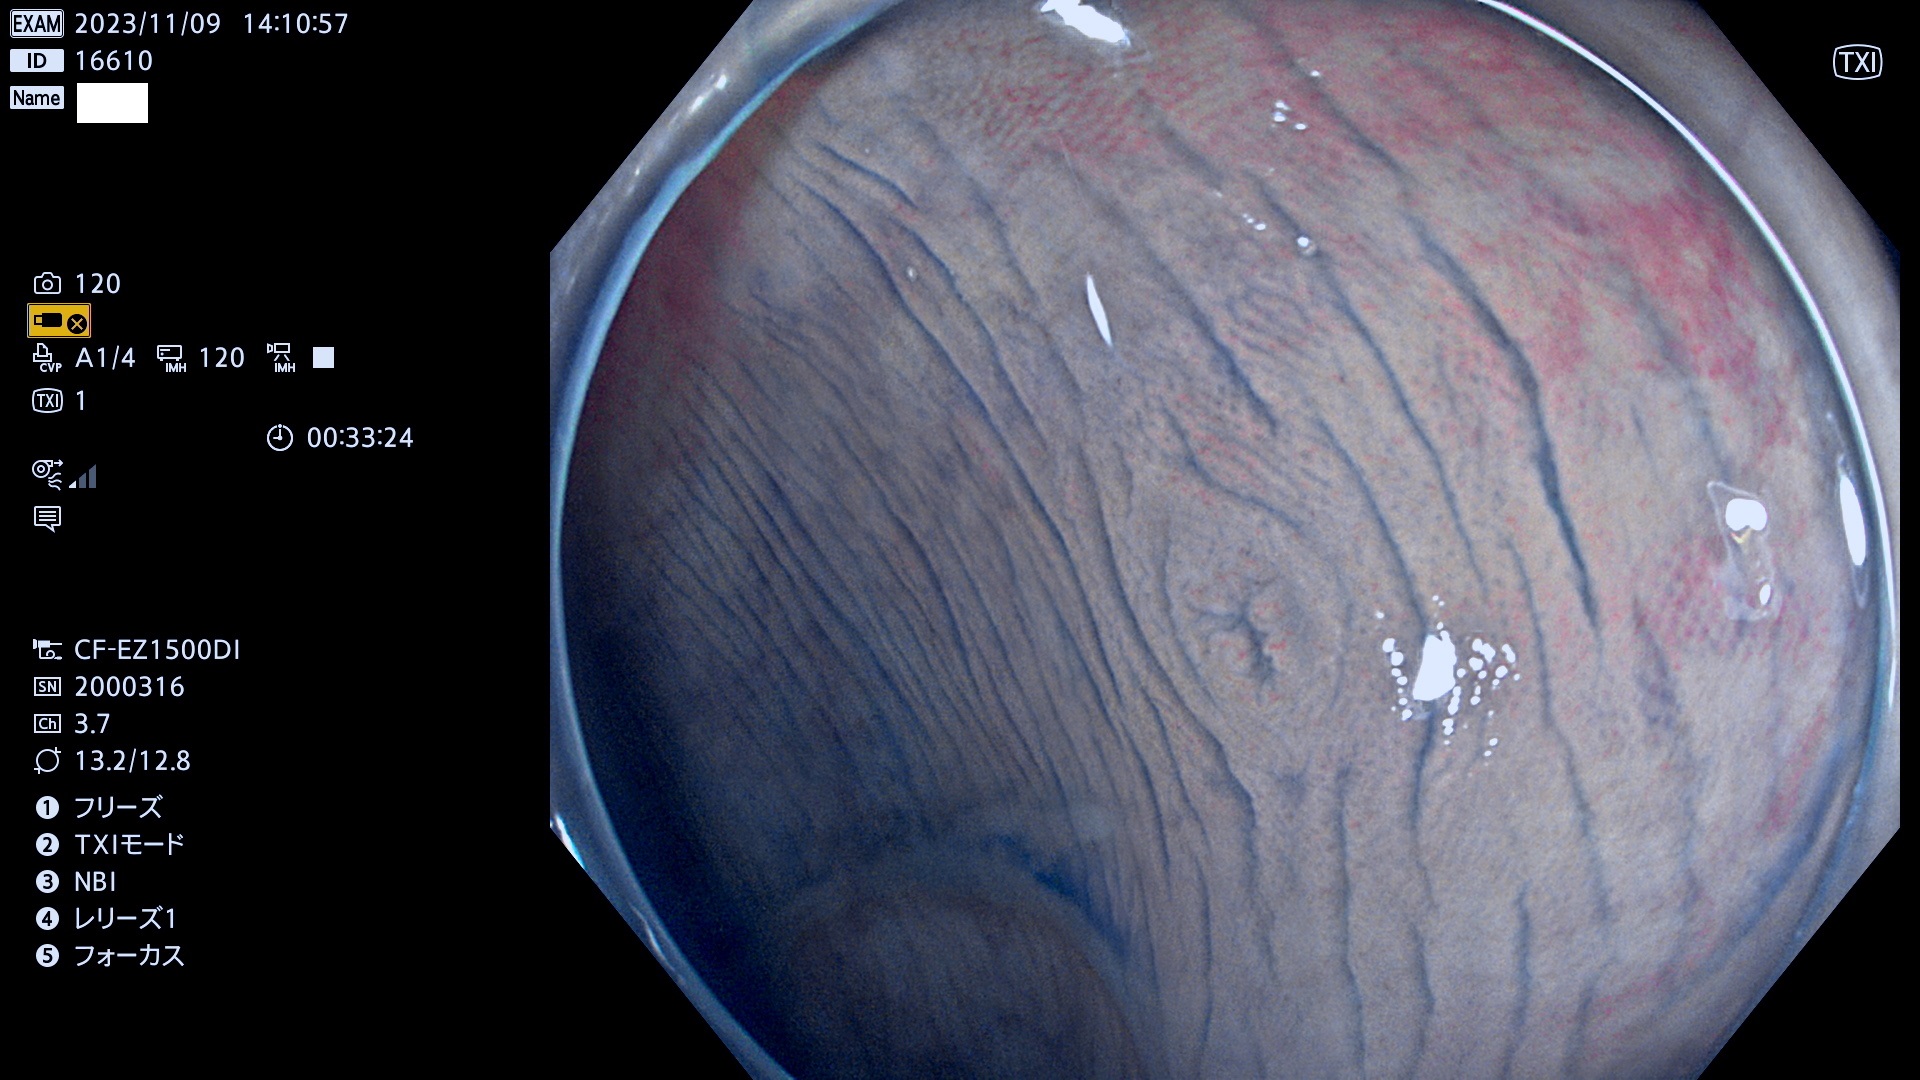

表面型腺腫(Flat Adenoma)の中で、完全に平坦な物をUb、陥凹している物をUcと呼びます。平坦隆起型(Ua)よりも、発見が難しく危険な病変です。このタイプは「内視鏡後・大腸癌の重要犯人」であり、この発見率は「腺腫発見率」よりも、重要な意味があります。

毎週の検査(木・金・土・日)に発見されたUb、Uc型・腺腫を、その週の日曜の夜にUPし1週間、提示します。

抽出の対象期間 2023年11月9日(木)〜11月12(日)の4日間(48件の検査)5件